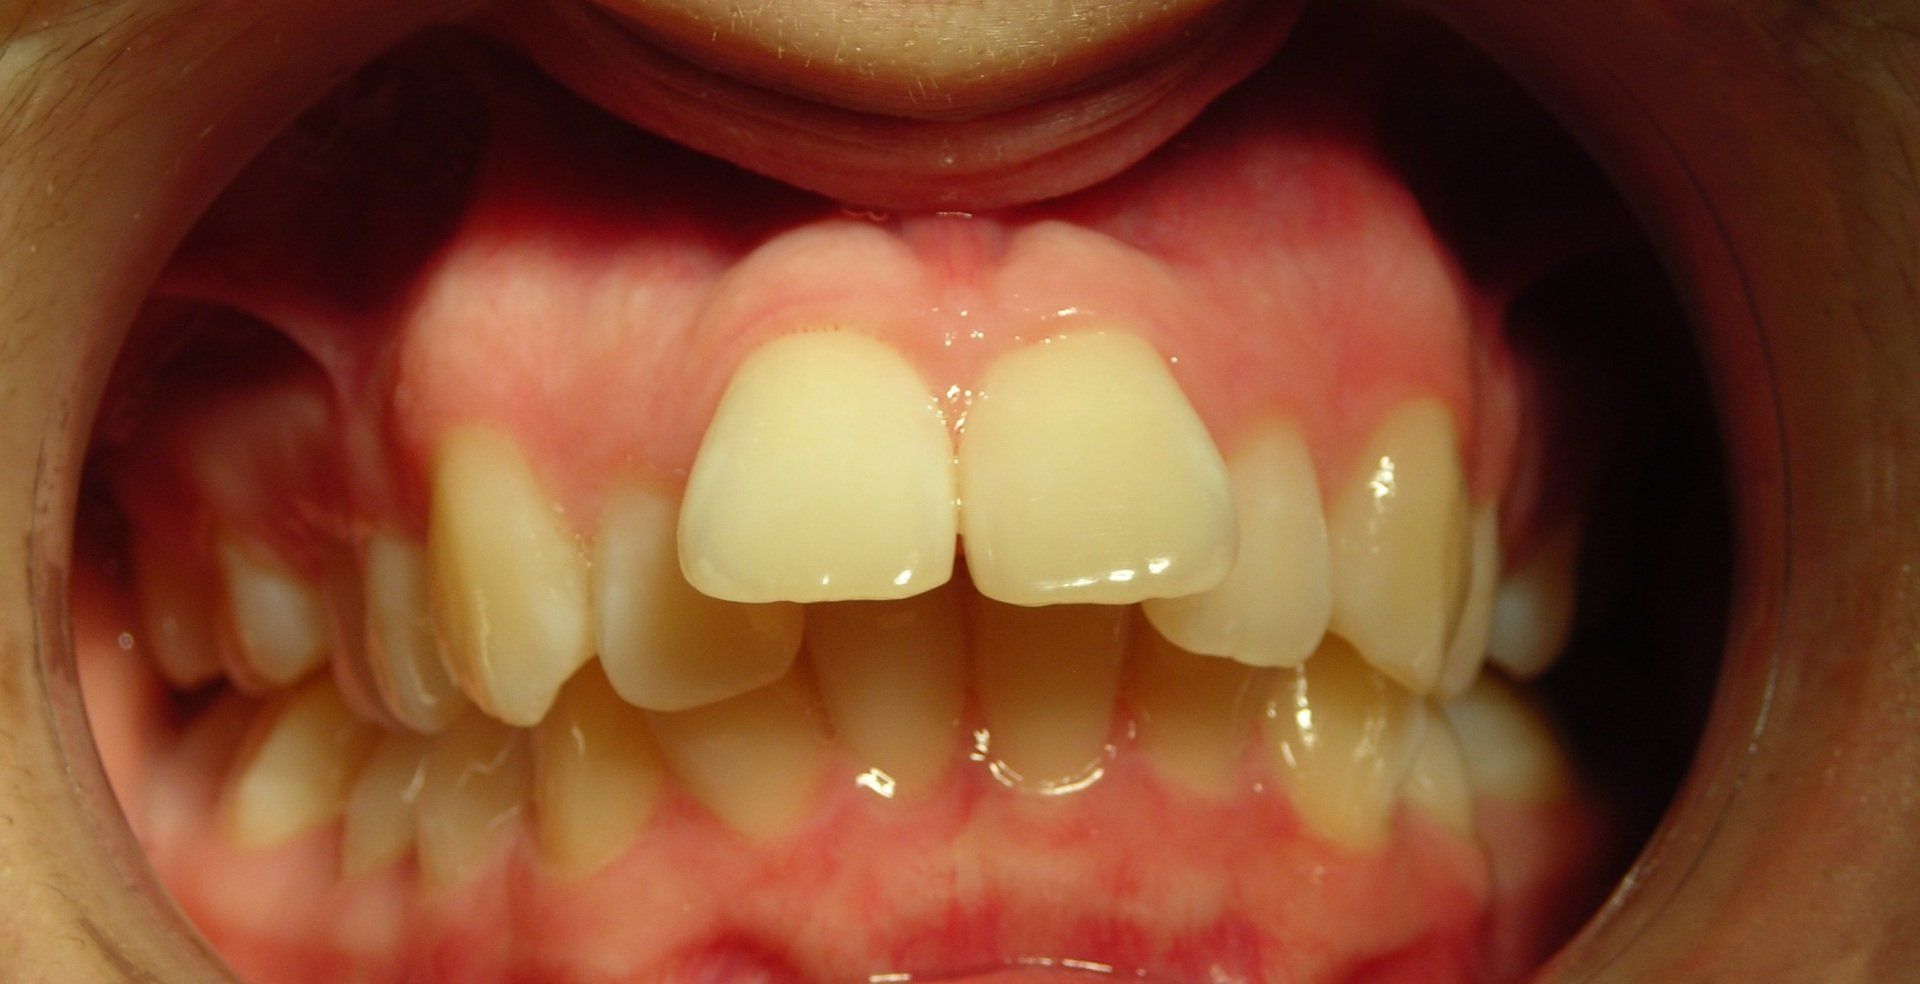

Servizi di ortodonzia

L'ortodonzia si occupa dello studio e della correzione della posizione anomala dei denti, delle malformazioni delle ossa mascellari e delle ricadute che queste hanno sull'aspetto del viso e sulle funzioni quali respirazione, masticazione e fonazione.

Nel nostro studio impieghiamo terapie ortodontiche sia chirurgiche che meccaniche, utilizzando apparecchi rimovibili, costruiti su misura secondo varie metodiche, oppure fissi, applicati sui denti.

Dentisti esperti in pedodonzia

La pedodonzia è l'applicazione delle conoscenze di base dell'odontoiatria, sia mediche che comportamentali, allo sviluppo normale o patologico del bambino, dalla nascita alla pubertà.

Nel nostro studio offriamo servizi specialistici per la prevenzione e la cura della carie dei denti decidui e permanenti, attraverso la pratica endodontica, la prevenzione ortodontica, il riconoscimento e la correzione precoce delle abitudini nocive e la traumatologia dentale.